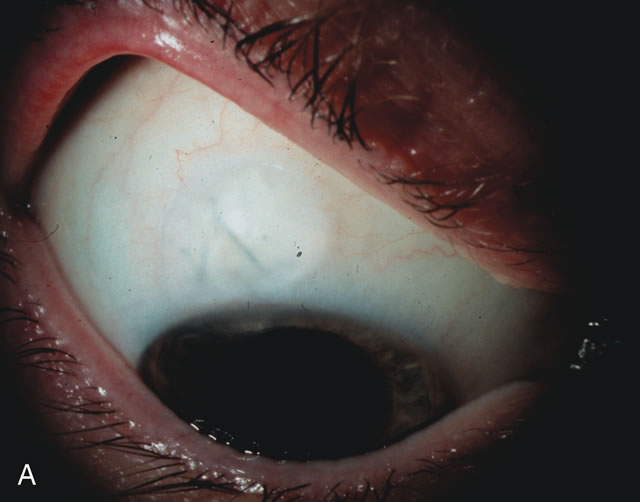

loss. The trend in conversion from extracapsular cataract extraction (ECCE) to small incision cataract surgery continues to improve visual outcomes. The benefits from small incision cataract surgery for the stable glaucoma patient are extraordinary. The capacity to immediately improve vision with small incision cataract surgery alone, avoid the complications of trabeculectomy, potentially lower intraocular pressure (IOP) over the long-term and spare valuable conjunctiva for future glaucoma surgery is a surgical triumph for these patients. Consequently, a stable glaucoma patient on one or two medications with mild disc damage and symptomatic cataract may no longer require a combined or staged procedure. When filtration surgery is required, the capability to modulate wound healing and alter aqueous flow after trabeculectomy decreases complications and increases efficacy. From a pharmacologic viewpoint, the potent prostaglandin analogues enhance outflow thereby decreasing the need for more complex filtration surgery. Patients with advanced disc damage, uncontrolled glaucoma at any stage, or complex cataracts present a much more challenging situation. They are far from elementary and present the ophthalmic surgeon and patient with many demanding problems. The knowledge and wisdom necessary to achieve a favorable outcome in these difficult cases requires a fusion of higher level preoperative, intraoperative, and postoperative decision-making skills. This situation is seen most commonly in patients requiring combined procedures who have advanced optic nerve damage complicated by any of the following: systemic diseases, especially diabetes mellitus; secondary glaucomas; anterior segment anomalies; miosis with posterior synechiae; pseudoexfoliation; keratopathy and complex cataracts. Society's perception of cataract surgery as a quick-fix operation with a rapid return of splendid vision is often not true for these patients who invariably perceive they are undergoing “routine” cataract surgery.1 Optic nerve damage or other concomitant eye diseases may limit visual recovery after flawless phacotrabeculectomy leaving a disappointed patient. Moreover, filtration surgery slows improvement in visual acuity.2,3 Informed consent with special emphasis on postoperative complications is especially important in glaucoma patients undergoing high-risk filtration surgery. Surgeons and their staff must spend additional time counseling patients who require filtration surgery due to the myriad of potential complications inherent to this procedure, which are far greater than routine lens extraction. In years past, patients with both cataract and glaucoma frequently provided overwhelming surgical challenges for the ophthalmologist. The ability to carry out phacoemulsification through a 3.2-mm corneal incision along with inserting a foldable IOL is a vast improvement over 11-mm incisions that were common a decade ago (Fig. 1). The anatomical and inflammatory changes to the eye are less with small incision techniques, improving the likelihood of success with concomitant glaucoma surgery. Pharmacologic inhibition of fibrosis along with postoperative wound revision increases the long-term success rate of filtration surgery when combined with lens extraction. (Fig. 2). The learning curve may be steep at times, but the blending of cataract and glaucoma surgical skills slowly falls into place as the surgeon constantly learns and upgrades his or her technique.